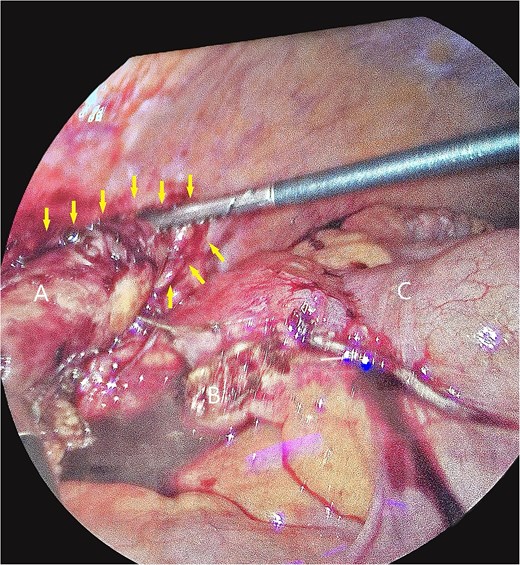

The patient underwent laparoscopic appendectomy with laparoscopic enterolysis. The appendix appeared inflamed, dilated, and gangrenous, with a perforation located 2 cm from the base. Notably, the appendix was not in a retrocecal position as initially suspected but was found to be herniating through a defect in the iliacus muscle (Fig. 3). The appendix was circumferentially freed from the hernia defect, which was identified as tracking cephalad between the iliacus muscle and the iliac bone. The hernia defect measured 2.5 cm and was primarily closed using two figure-of-eight 2–0 Vicryl sutures, leaving a small inferior opening to allow for drainage (Fig. 4). A 19 Fr Blake drain was placed in the right lower quadrant and paracolic gutter.

Iliacus hernia defect closed primarily after appendix was removed.